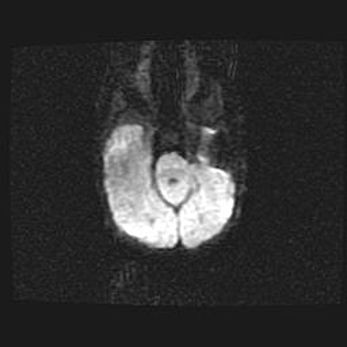

Церебральная ишемия II.

Возраст: 7 дней

Вес: 3350 г

Пол: женский

Окружность головы: 35 см

Срок гестации: 39 недель

Ишемия головного мозга – это состояние, которое развивается в ответ на кислородное голодание вследствие недостаточного мозгового кровообращения. У новорожденных она является следствием дефицита кислорода, что ведет к метаболическим расстройствам различной степени тяжести в тканях головного мозга, в том числе к развитию коагуляционных некрозов и гибели нейронов.